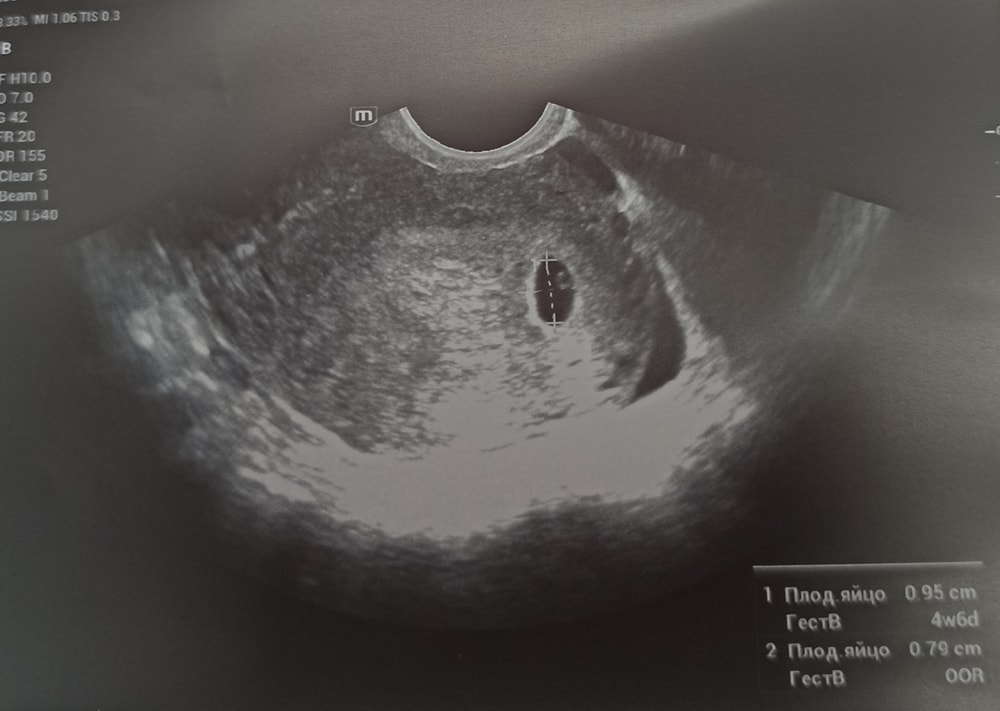

Первое узи🥰 22 дпо

УЗИ, КТГ, доплерСегодня 26 ноября сходила на УЗИ🥰🤗

Срок по последним месячным сегодня ровно 6 недель. Овуляция была поздняя на 20-21 ДЦ.По овуляции 5 недель. По УЗИ 5 недель. 🤗

Беременность маточная.

Эндометрий 18 мм. Желточный мешочек 3.7мм. Диаметр плодного яйца 9.5 мм